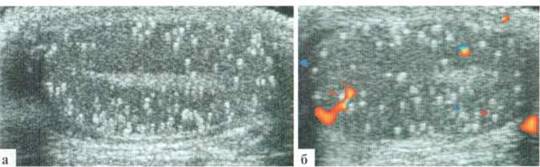

ОРГАНЫ МОШОНКИ: яички в мошонке, размеры в пределах возрастной нормы. Структуры яичек хорошо дифференцированы. Контуры ровные, сохранены. Паренхима гомогенная, с мелкоточечными множественными (без счета) эхогенными включениями без акустических теней в обоих яичках. Справа определяется резкое утолщение и гиперемия оболочек яичка, небольшое количество жидкостного компонента в оболочках. В нижних отделах оболочек — включение пониженной эхогенности размерами около 11x7 мм, бессосудистое. Сосудистый рисунок в придатке усилен (рис. 6.7). Других дополнительных организованных структур в оболочках, проекции семейных протоков и сосудов не выявляется. Интратестикулярный сосудистый рисунок сохранен с обеих сторон. Структуры визуализируемых участков сосудов не изменены.

ЗАКЛЮЧЕНИЕ: эхопризнаки тестикулярного микролитиаза с обеих сторон (генерализованная форма), содержимого в оболочках яичка справа (гной), воспалительных изменений оболочек правого яичка (абсцесс мошонки).

Рис. 6.7. Клинический пример № 41: а — левое яичко; б, в, г — разные сканы правой половины мошонки